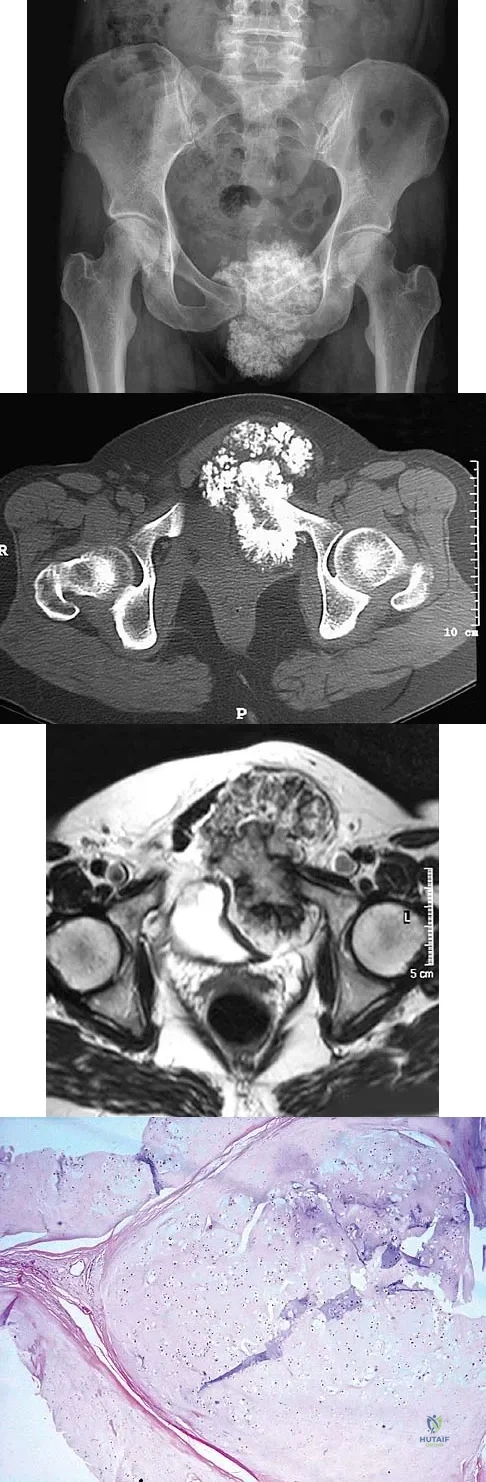

A 47-year-old woman has an asymptomatic pelvic mass that was discovered on routine gynecologic examination. A radiograph, CT scan, MRI scan, and biopsy specimen are shown in Figures 7a through 7d. Metastatic work-up is negative. Treatment should consist of